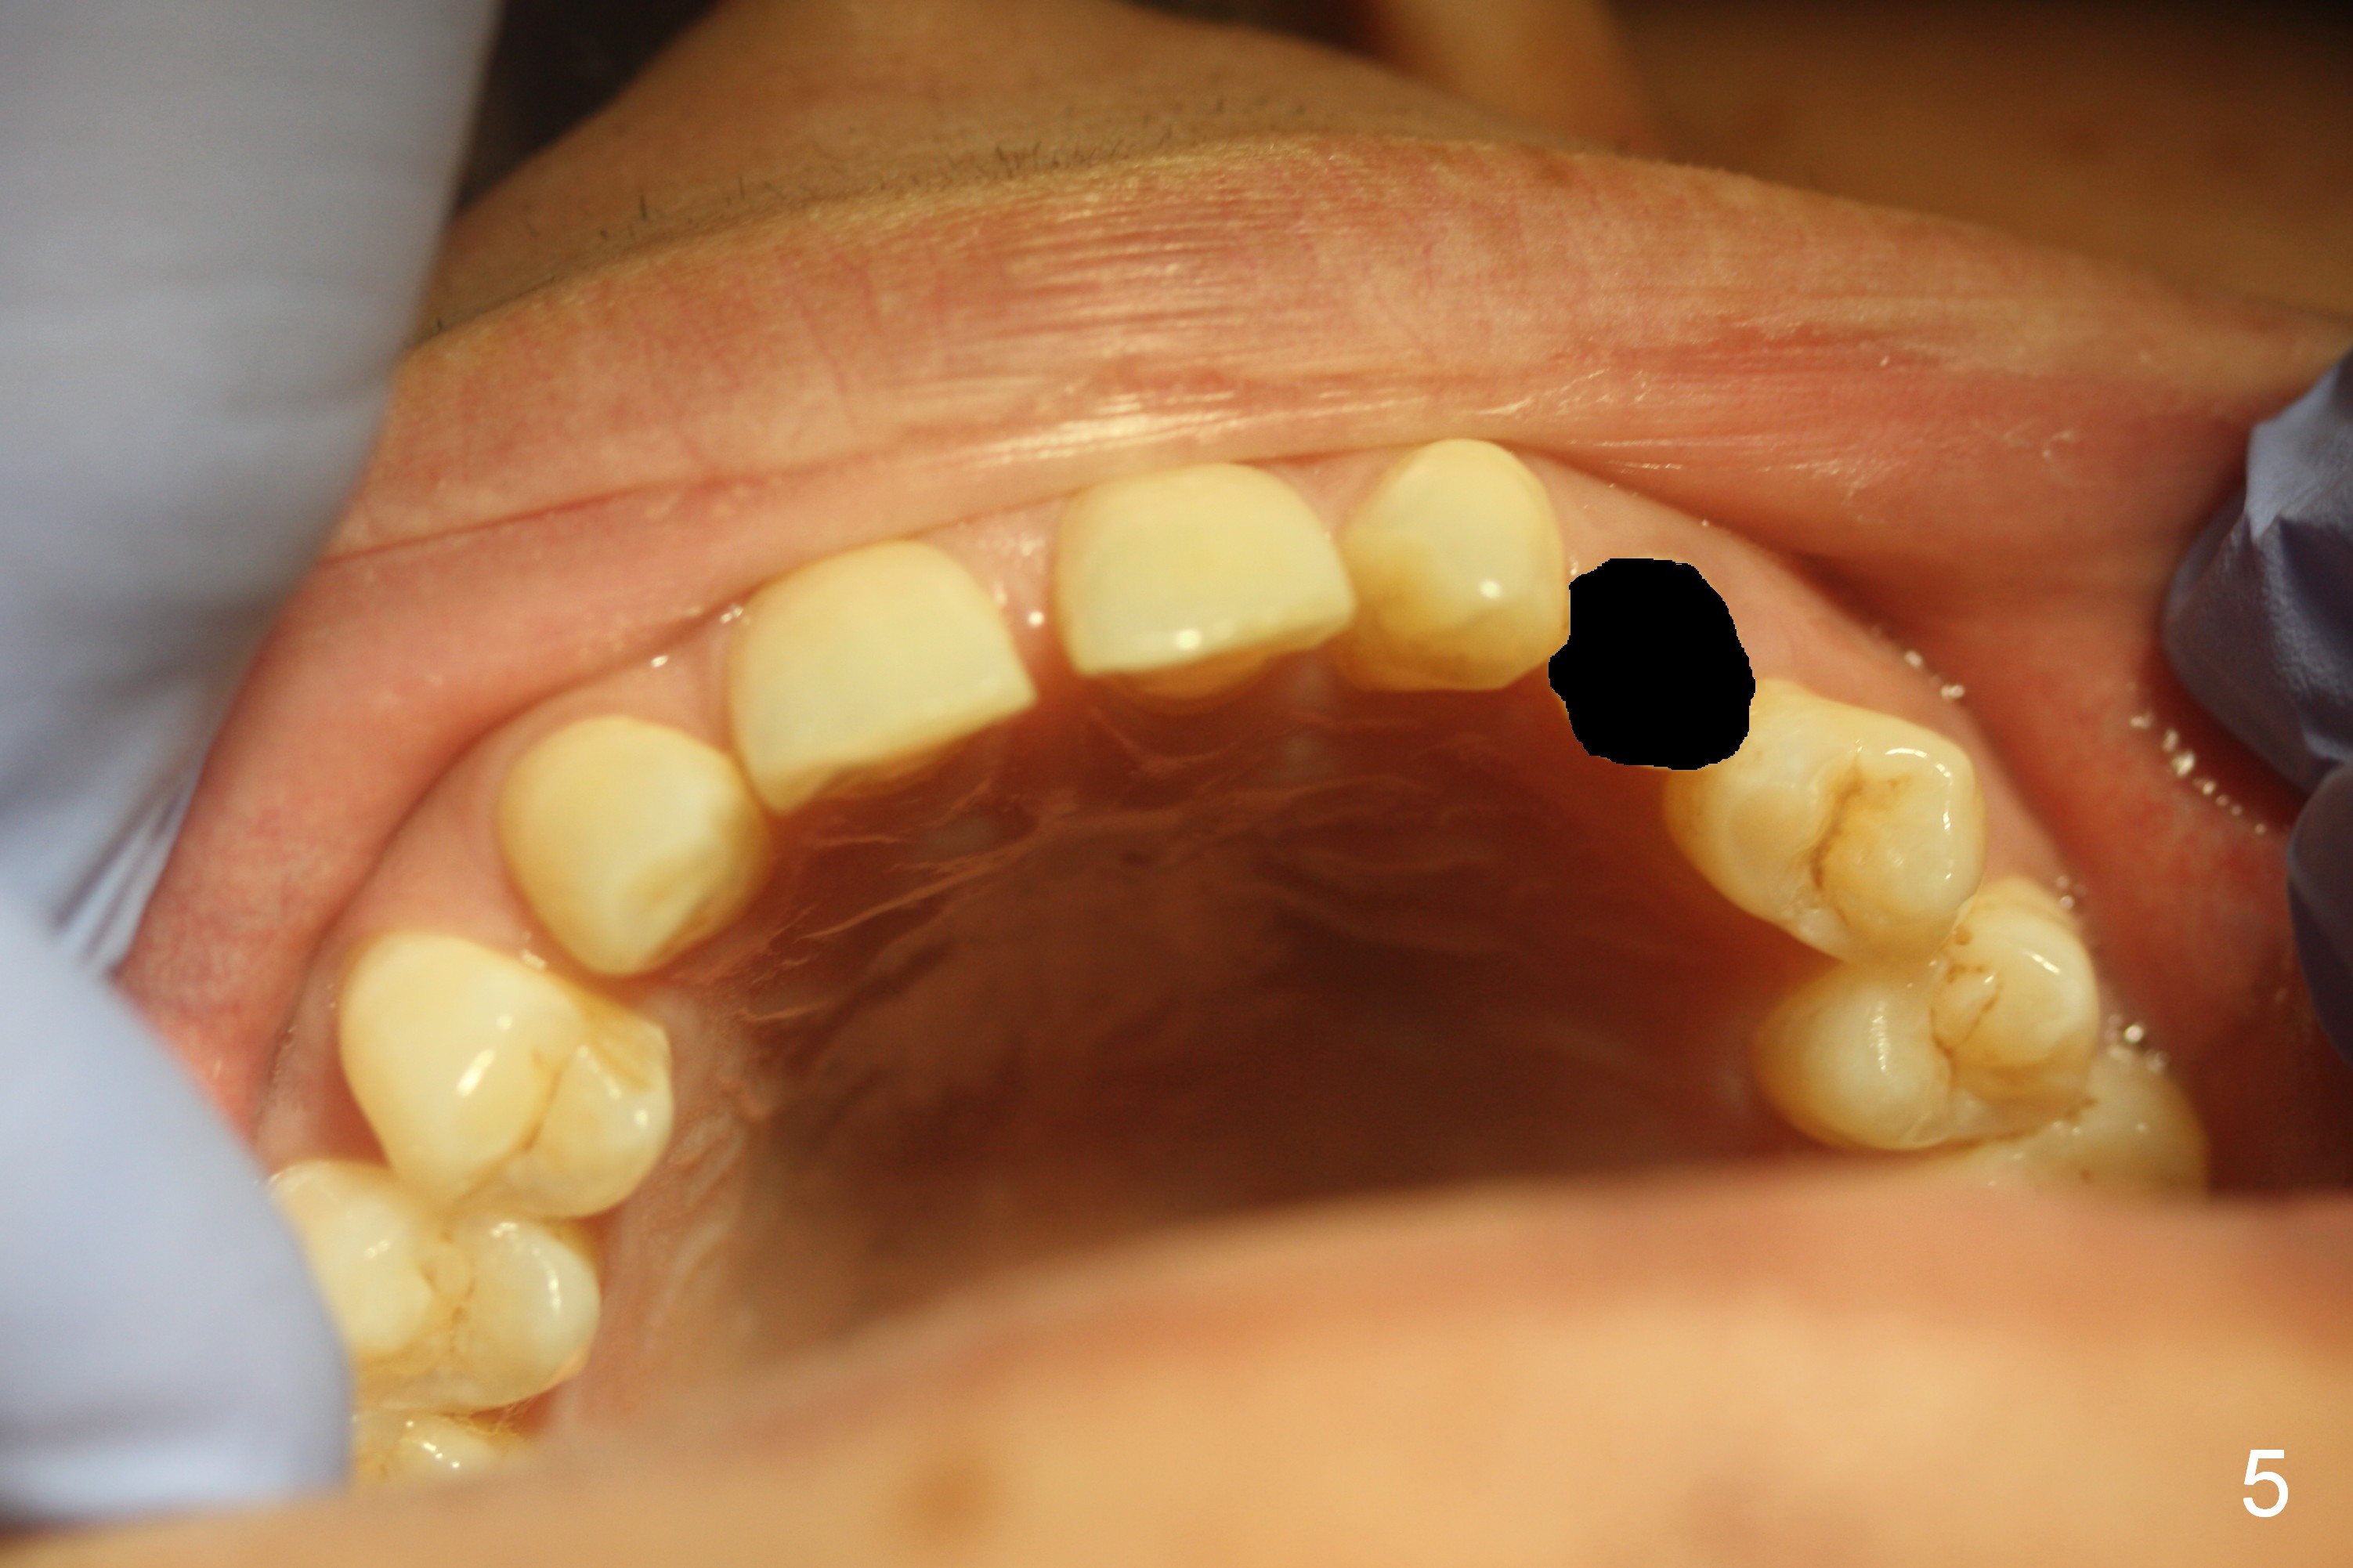

A 38-year-old man has congenitally missing laterals (Fig.1,2) with retention of a deciduous canine (Fig.2,3 C). UL 4 (upper left 1st bicuspid) rotates (Fig.3). LR7 has been extracted (Fig.4).

To improve cosmetics, extract the deciduous tooth (Fig.5), place brackets for the maxillary teeth (6-6), including a lingual button on UL4 to correct the rotation and distalize U3s (Fig.6), close the upper midline diastema and change the midline if needed (Fig.7) and finally place small-diameter implants at U2s (Fig.8 white circles).